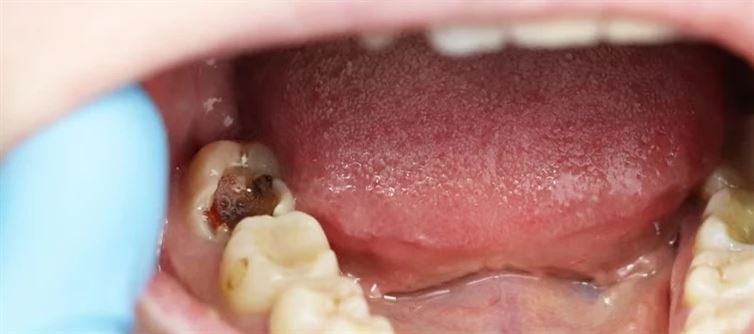

Your teeth progressively become hollow from the inside due to a variety of factors, including a busy lifestyle, the fast food trend, eating too much sugary and sticky food, and neglecting to brush your teeth. The enamel, the outermost coating of teeth, is harmed when oral bacteria turn certain meals into acid. At first, it is not felt, but as the decay worsens, symptoms like hot and cold feelings, chewing pain, and foul breath start to show.

The National Institute of Dental and Craniofacial Research (NIDCR) states that fluoride therapy can stop tooth decay if it is detected early. However, the dentist must extract the rotted portion and fill it in when the decay worsens and a cavity forms in the tooth.